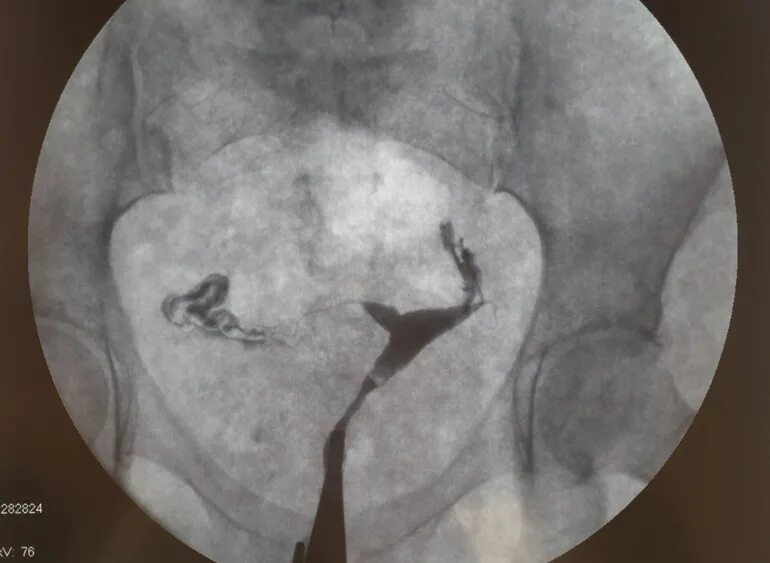

Реканализация фаллопиевой трубы. гистеросальпингография маточных труб. гистеросальпингография непроходимость.